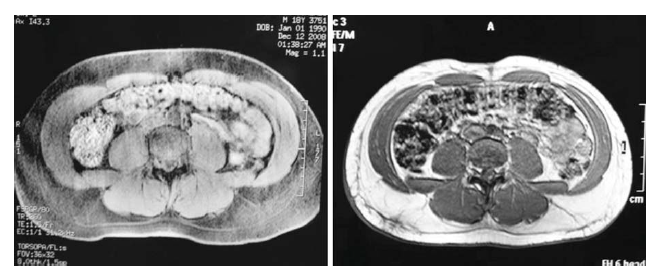

A Safety and Feasibility Study of a Novel Radiofrequency-Assisted Liposuction Technique

From July to December of 2008, 23 subjects underwent radiofrequency-assisted liposuction using the BodyTite system. Information regarding aesthetic results and local and systemic complications was collected immediately after the procedure and at 6- and 12-week follow-up. The authors' study suggests that the removal of moderate volumes of fat with concurrent subdermal tissue contraction can be performed safely and effectively with radiofrequency-assisted liposuction. Additional benefits of this technique are excellent patient tolerance and fast recovery time. Nonetheless, a larger sample is required to confirm the authors' results and guarantee the efficacy and safety of the procedure. Direct comparison with traditional liposuction or energy-assisted liposuction techniques may provide some insights to tailor future indications of this novel technique.